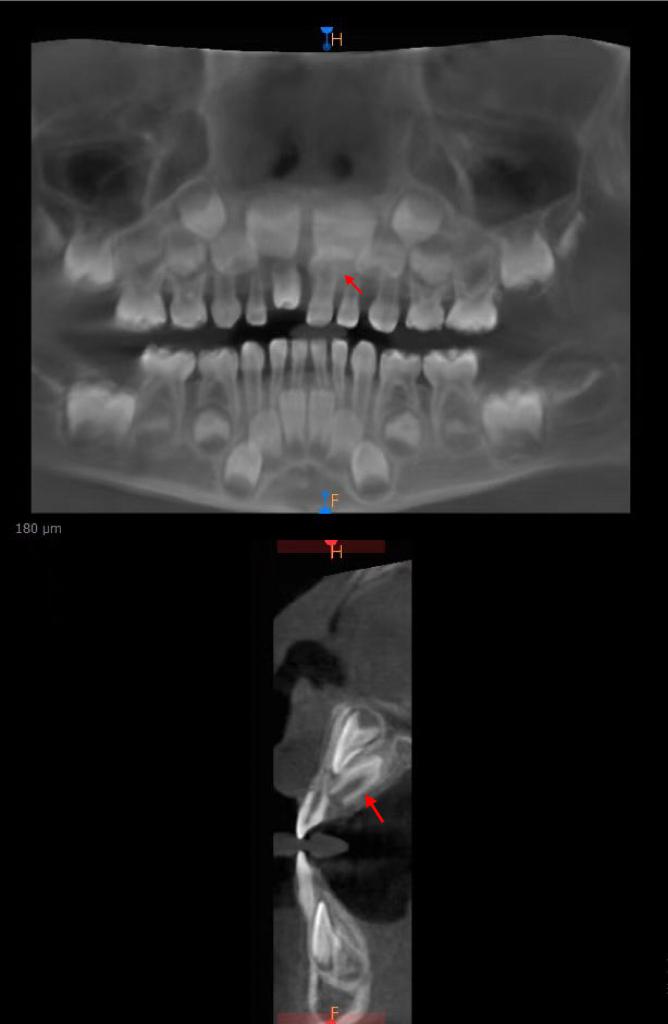

箭头所示为倒置生长的埋伏多生牙

接诊的何孔炎主任医师在仔细检查后发现,这颗新牙极有可能是一颗多生牙。经家长同意,医院立即为孩子进行了口腔三维CT检查。结果证实了医生的判断:这颗形态异常的牙齿确为多生牙,而本该在此萌出的正常恒牙胚,正被它“压制”在下方。

箭头所示为已萌出多生牙

更为惊人的是,CT影像还揭示了另一个隐藏的“秘密”——在患儿左侧门牙牙根舌侧,竟还倒置生长着另一颗埋伏的多生牙。这颗牙齿犹如一颗“定时炸弹”,向上生长,极可能影响未来恒牙的正常萌出。